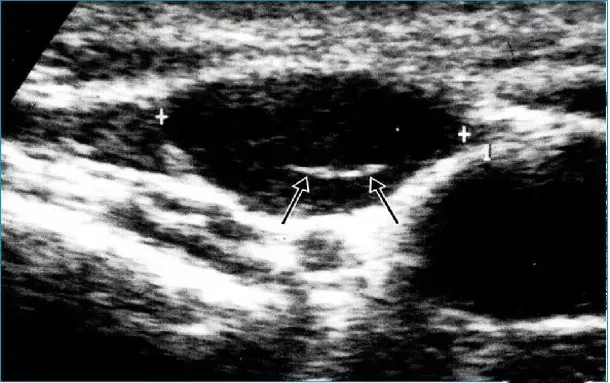

● 淋巴结不同程度肿大,多呈椭圆形,纵横比>2。

● 被膜光滑,边界清楚,淋巴结之间无融合。

● 皮质增厚呈低回声,髓质居中、增厚,呈高回声。

● 淋巴结内血流信号明显增多,沿门部呈放射状、树枝状分布。

● 动脉血流为低阻型频谱。

● 脓肿形成时淋巴门消失,结内可见含细点状回声的液性暗区,加压可见漂动,病变严重时可突破被膜。

病例:右侧颈部肿痛3天,颈部可触及多个痛性结节。

超声描述:右侧颈部Ⅲ、Ⅳ区可见多发肿大的淋巴结,大者约21x6mm,呈椭圆形,皮质增厚,髓质居中,内部血流信号明显增多,呈放射状分布。